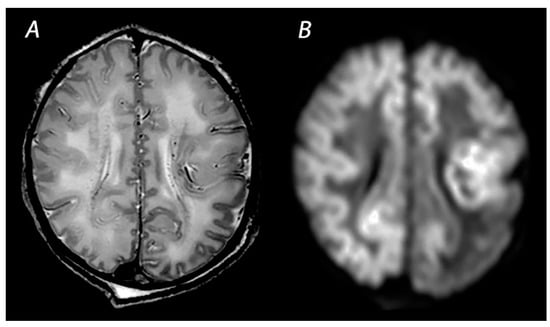

2.2. White Matter/Watershed (WM/WS) Predominant Pattern of Injury

| WM/WS | T1WI/T2WI | Abnormal signal intensity in the white matter of the watershed areas of the cerebral arteries, and also the overlying cortex in severely affected infants. T2WI may show loss of gray-white matter differentiation at the cortex. | Inconspicuous or subtle abnormalities in the first days, which become gradually more apparent by the latter half of the first week following the insult. MRI obtained beyond 1 month can show cortical thinning, white matter volume loss, cysts and gliosis of the cortex and white matter. |

| DWI | High signal intensity on isotropic DWI with low ADC values in the affected areas. | Abnormalities peak at 3–5 days after the insult. Pseudo-normalization occurs after approximately 11–12 days for infants treated with therapeutic hypothermia, and 6–8 days in non-cooled infants. | |